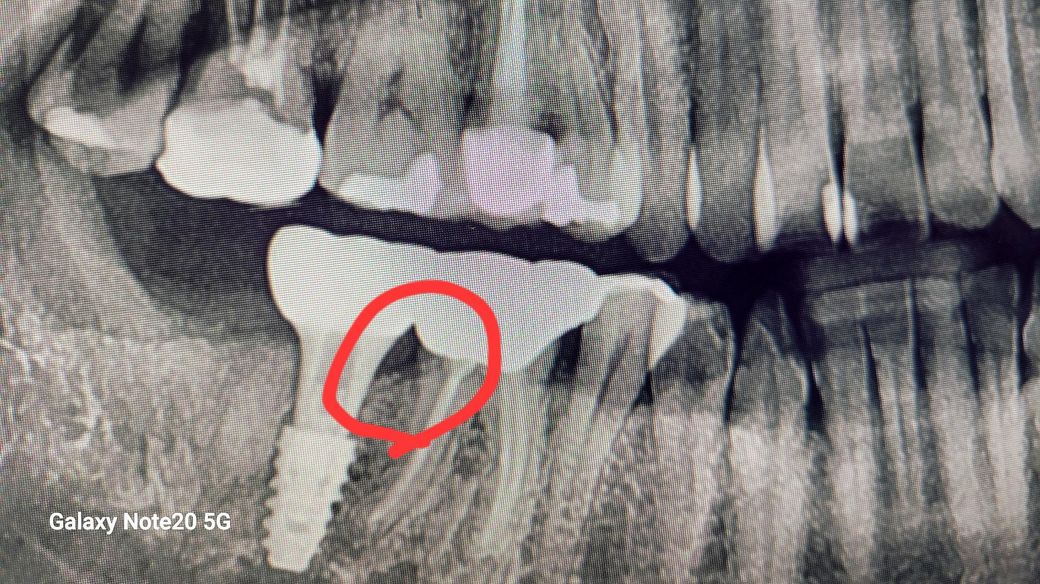

얼마전 그부위로 씹을때마다 잘끼고 결국 염증이생겨서 다시 그치과갔는데 임플란트한것은 문제없고 그밑의 공간이커서 음식물이 잘끼일수밖에 없다고 잘관리해주는 방법뿐이라는 답을받았는데 고기뿐아니라 나물같은것. 그부위로 과자같은것도 씹어먹을때도 통증있는데, 그럼그부위로는 거의못씹나요? 치료부위가 원래 염증이 엄청심하긴했습니다.

• 1번 째 사진

엑스레이상 임플란트 부위 염증이 있는 것으로 보이진 않습니다만 교합시 지속적인 통증이 있다면 골유착이 안된 것일 수도 있습니다